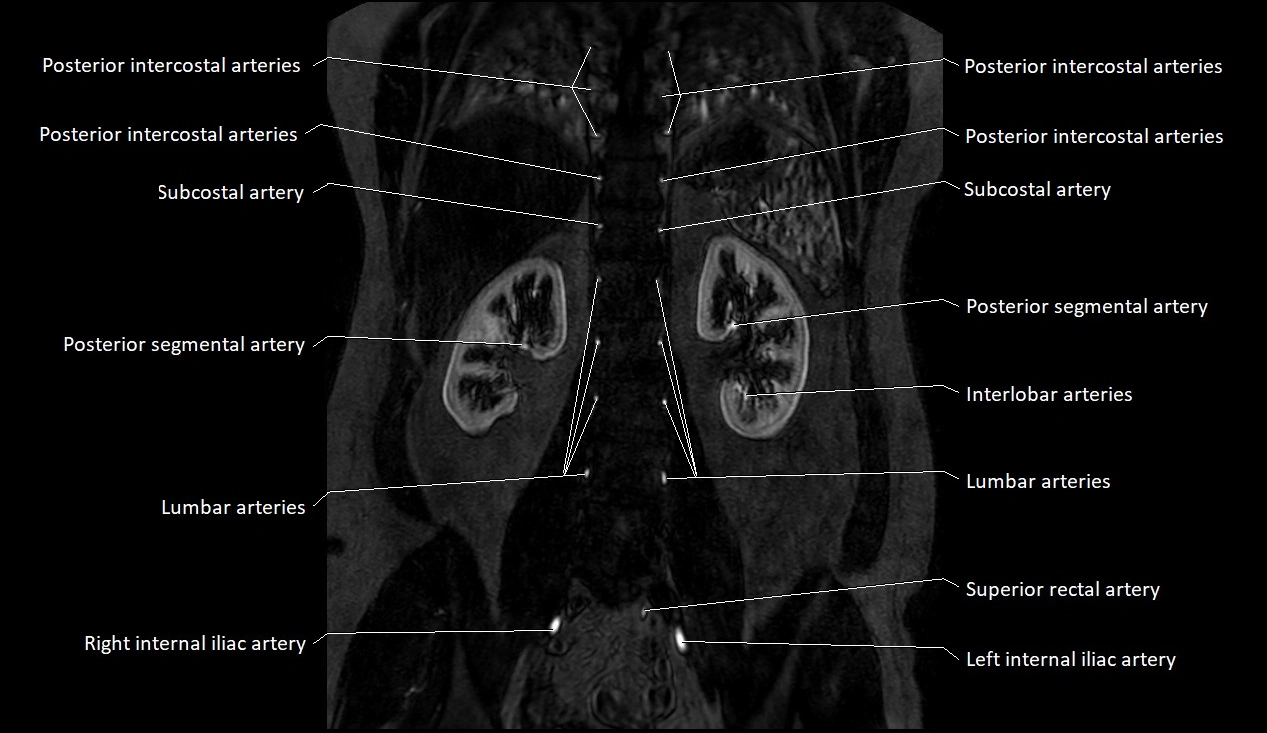

MRI images

image